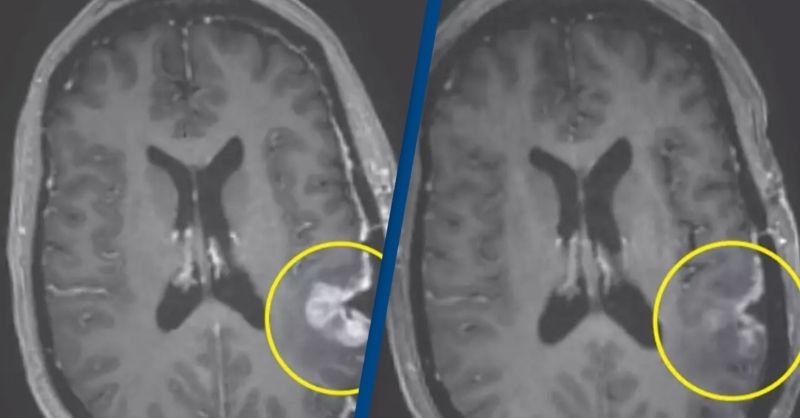

Doctor remains cancer-free one year after using world-first treatment he developed for terminal brain tumor

A doctor has provided an update one year after becoming the first person to receive a groundbreaking treatment for his terminal brain cancer. Richard Scolyer, a globally recognized...